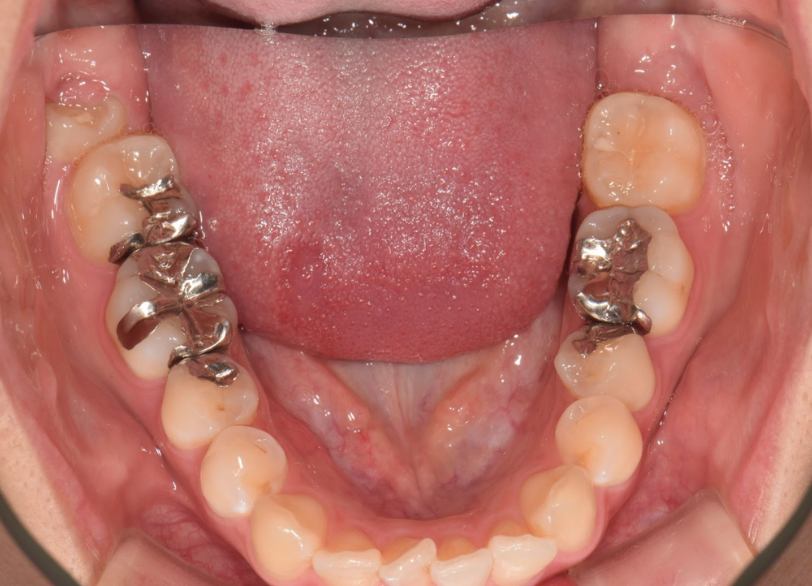

矯正治療、かみ合わせの治療 2019.07.17矯正歯科治療の症例 矯正治療、かみ合わせの治療の治療例です。費用:40万治療期間:1.5年リスク説明:元々顎関節症などの顎の疾患がある場合には治療期間が延びることがあります。後戻りを避けるため固定をしないといけない場合があ... 続きを読む